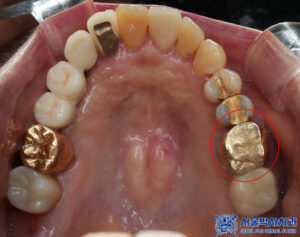

치유기간을 기다린 후

위쪽도 본원 원내기공소에서

직접 제작한 개인 맞춤형

임플란트 보철물을

세팅해 드렸습니다.

마무리 후 사진입니다.

환자분께 골다공중 주사제 체크를 잘하여

안정적으로 임플란트 수술을

할 수 있게 도와드렸고

무절개임플란트 후

만족도가 매우 높으셨습니다.